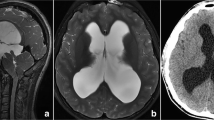

Pre-, postoperative and 3-months mid-sagittal CISS* magnetic resonance images of a 27 year old patient, who showed a preoperative Heidelberg score of + 2 (TVF** + 1 and LT*** + 1) (A), postoperatively, the TVF and LT went to a grade of 0 each, thus the postoperative Heidelberg score was 0, as seen in the middle image (B). After three months, the LT showed a reduction such that the Heidelberg score decreased to -1 as shown in the right image (C)